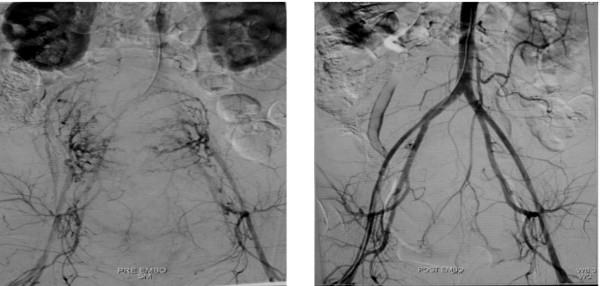

| Hình ảnh động mạch tử cung đang xuất huyết (bên trái) và khi không còn xuất huyết |

Các bác sĩ đã lần đầu áp dụng kỹ thuật thuyên tắc động mạch tử cung. Sau 30 phút thao tác, tình trạng băng huyết của sản phụ chấm dứt và phục hồi tốt.

Cùng ngày, sản phụ 34 tuổi cũng băng huyết sau sinh tại bệnh viện. Trong hai giờ sau cuộc mổ bắt con, sản phụ mất khoảng 1,5 lít máu, dùng thuốc gò tử cung nhưng tử cung không co hồi tốt nên bác sĩ chỉ định thuyên tắc mạch. Cả hai bệnh nhân đều ổn định và hồi phục tốt, dự kiến sẽ xuất viện trong tuần này.